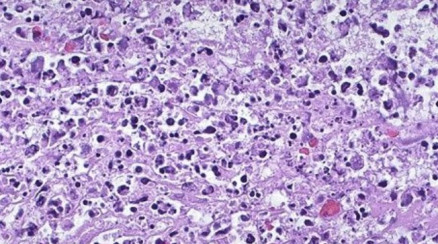

形态学变化

形态学观察细胞凋亡的变化是多阶段的,细胞凋亡往往涉及单个细胞,即便是一小部分细胞也是非同步发生的。首先出现的是细胞体积缩小,连接消失,与周围的细胞脱离,然后是细胞质密度增加,线粒体膜电位消失,通透性改变,释放细胞色素C到胞浆,核质浓缩,核膜核仁破碎,DNA降解成为约180bp-200bp片段;胞膜有小泡状形成,膜内侧磷脂酰丝氨酸外翻到膜表面,胞膜结构仍然完整,最终可将凋亡细胞遗骸分割包裹为几个凋亡小体,无内容物外溢,因此不引起周围的炎症反应,凋亡小体可迅速被周围专职或非专职吞噬细胞吞噬。

3.透射电子显微镜观察

结果评判:凋亡细胞体积变小,细胞质浓缩。凋亡Ⅰ期(pro-apoptosis nuclei)的细胞核内染色质高度盘绕,出现许多称为气穴现象(cavitations)的空泡结构;Ⅱa期细胞核的染色质高度凝聚、边缘化;细胞凋亡的晚期,细胞核裂解为碎块,产生凋亡小体。